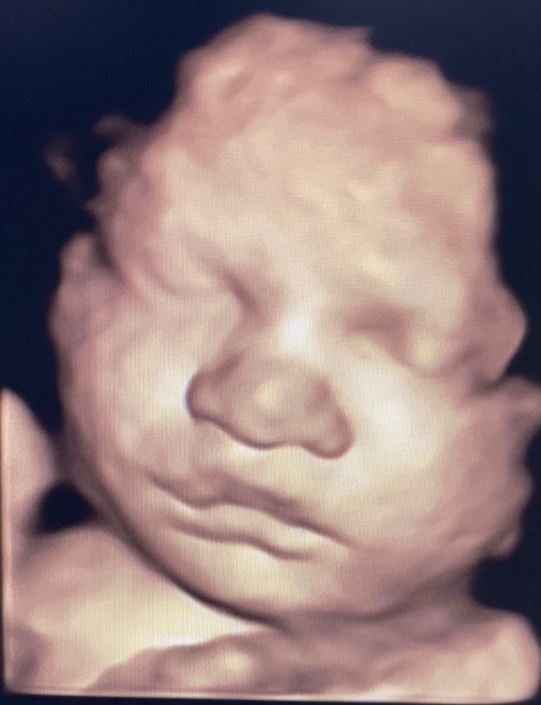

Prenatal Peek is the leader in 3D 4D Ultrasound. We employ only Certified / Registered Sonographers maintaining unsurpassed standards in 3D ultrasound. You deserve the best! Call us today.